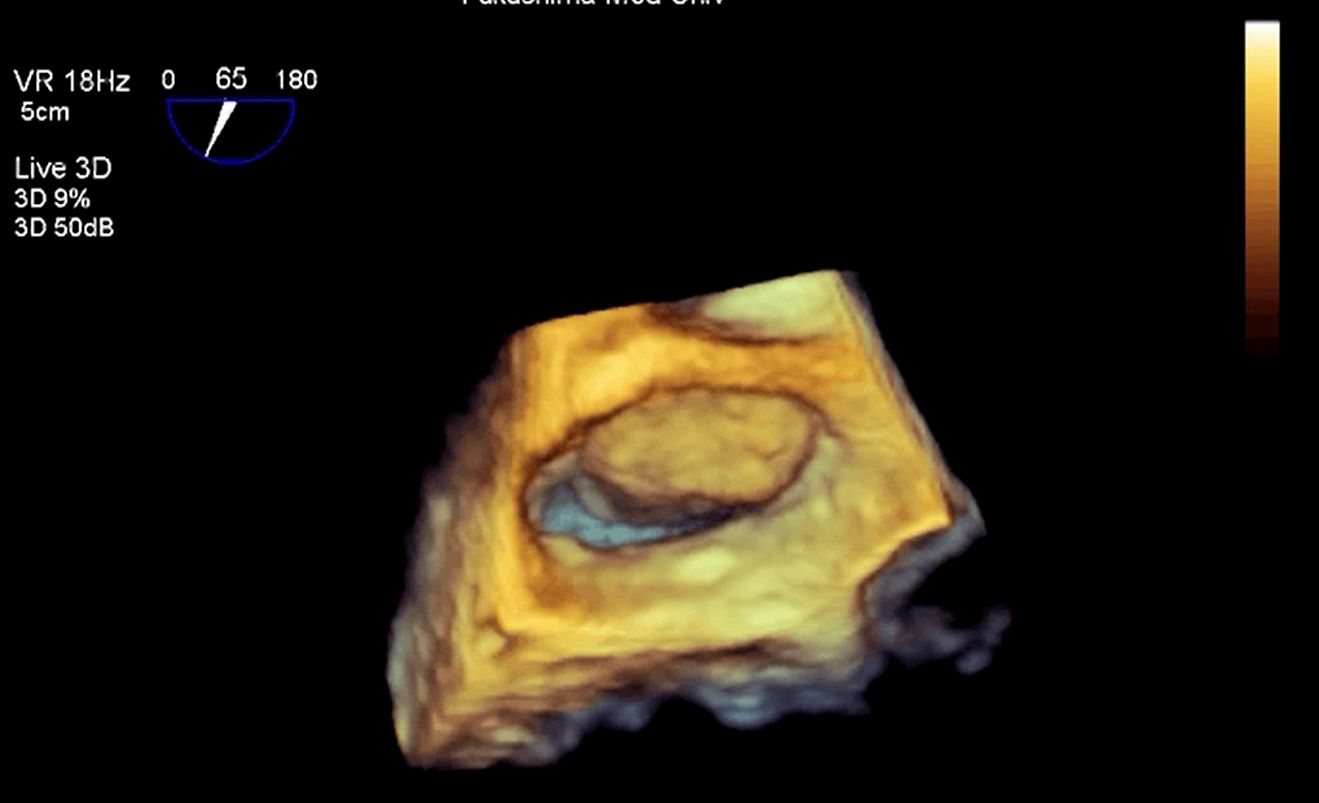

3D画像

心房中隔欠損症

僧帽弁置換術後(機械弁)